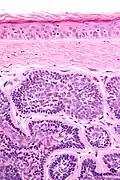

Dermal cylindroma. Hyaline droplets visible in lobules.

Dermal cylindromas are:

- Dermal lesions consisting of nests of cells that are surrounded by hyaline (i.e., glassy, eosinophilic, acellular) material and have:

- Hyperchromatic nuclei that may palisade (columnar nuclei arranged around the periphery of the cell nests with their short axis tangential to the nest periphery), and

- Cells with lighter staining ovoid nuclei at their centre.